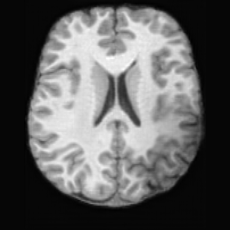

Pathology-to-Healthy Editing. Fig. 5 (a) presents comparison results on four input brain images with lesions of varying sizes, shapes, and densities. All competing models, although specialized for healthy brain image synthesis, struggle to reconstruct pathological regions, especially near lesion boundaries. In contrast, USB accurately reconstructs the corresponding healthy brain, even in challenging cases with large, high-density lesions where normal brain structures are almost completely obscured (last row). Tab. 2 provides a quantitative comparison for pathology-to-healthy editing, where USB achieves the best performance across all three datasets, demonstrating the effectiveness of its unified framework in reconstructing healthy brains from pathological inputs. Additional results are in Suppl. B.

Healthy-to-Pathology Editing. As shown in Fig. 5 (b), given a healthy brain image paired with a random lesion mask, USB seamlessly embeds the lesion into the healthy anatomy, producing realistic pathological appearances consistent with surrounding structural context. Yet UNA’s syntheses are visually unrealistic, with the conditioned lesion mask simply overlaid as a parallel layer onto the healthy brain. Tab. 3 further demonstrates USB’s superior performance. The evaluation was conducted on 100 pairs of lesion masks and healthy brains, with real stroke images

(a)PathologicalInput ImageSynthSR [18]Brain-ID [28]UNA [30]USBHealthyGround TruthRefer to captionRefer to captionRefer to captionRefer to captionRefer to captionRefer to captionRefer to captionRefer to captionRefer to captionRefer to captionRefer to captionRefer to captionRefer to captionRefer to captionRefer to captionRefer to captionRefer to captionRefer to captionRefer to captionRefer to captionRefer to captionRefer to captionRefer to captionRefer to caption(b)HealthyInput ImageConditionalLesion MaskUNA [30]USBRefer to captionRefer to captionRefer to captionRefer to captionRefer to captionRefer to captionRefer to captionRefer to captionRefer to captionRefer to captionRefer to captionRefer to captionRefer to captionRefer to captionRefer to captionRefer to caption

Figure 5: Comparison of bidirectional brain editing. (a) pathology-to-healthy, the circles and arrows highlight lesion regions and unsuccessful reconstructions; (b) healthy-to-pathology. Note that SynthSR and Brain-ID cannot perform healthy-to-pathology editing.